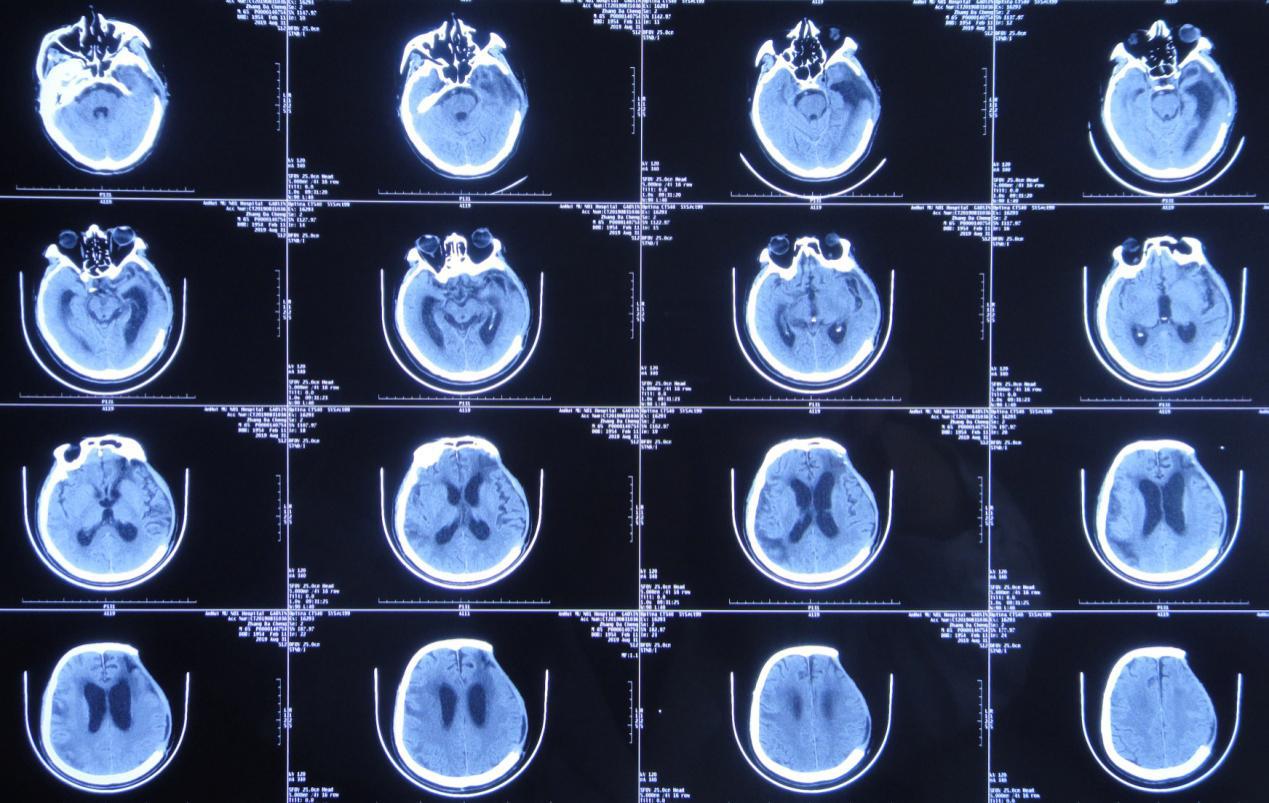

入院时:体温高达38.9℃,呈昏迷状态,疼痛刺激时四肢未见活动;颈稍抵抗,双下肢Babinski征未引出( 图-16 );头颅CT( 图-17 )示脑室腹腔分流术后改变,脑室扩张,脑室周围水肿。

图-17: 2020年1月31日头颅CT

入院第2天,即2020年2月1日行右侧脑室外引流术,术中拔除原脑室腹腔分流管,术后当日复查头颅CT( 图-18 )呈术后改变。

图-18: 2020年2月1日头颅CT术后

经过17天的治疗,于2020年2月18日行脑室腹壁外引流术,术后当日复查头颅CT( 图-21 )呈脑室引流术后改变,脑室较前缩小,脑室周围水肿减轻。

图-21: 2018年2月18日术后头颅CT

2020年4月27日,复查头颅CT( 图-23 )示脑室系统基本恢复正常。于2020年4月28日(即入院第88天,脑室外引流术第87天,脑室腹壁外引流术后69天)行脑室腹腔分流术,术后病情恢复良好。

图-23: 2020年4月27日头颅CT

经过李小勇脑脊液科98天的精心治疗,患者于2020年5月8日出院。出院前查头颅CT( 图-24 );出院时已能独立行走( 图-25 )。

图-24: 2020年5月7日出院前头颅CT